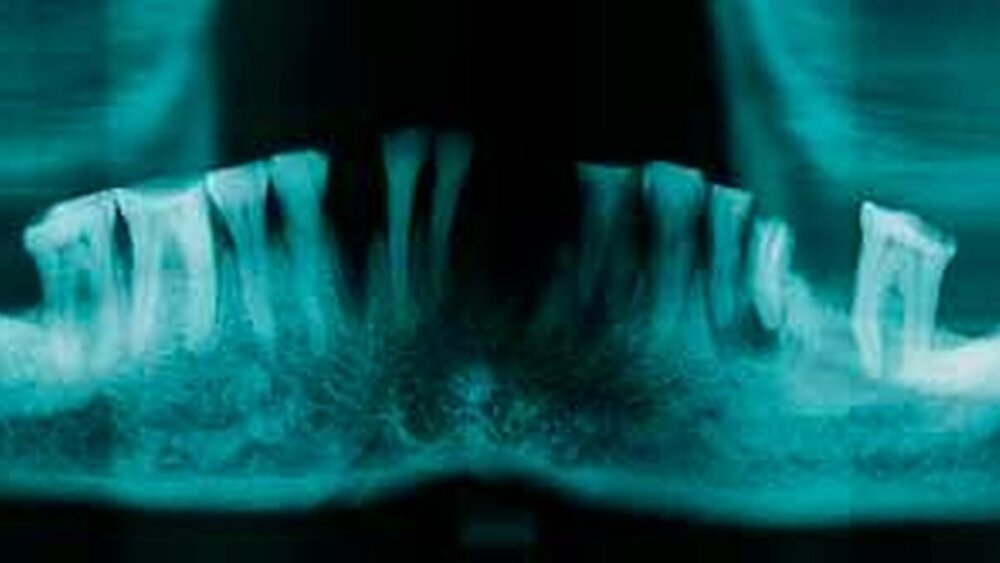

Die Abb. 1, 2 und 3 entsprechen einem nicht datierten Schädel mit Spuren der Mumifizierung. Augenfällig sind die überwiegenden Defekte im Kronenbereich, im Unterkiefer meist als starke Abrasion dargestellt (das Fehlen von Zähnen ist auch hier überwiegend als postmortal einzustufen, ausgenommen der ossifizierte Bereich anstelle des Molaren 36). Wurzelreste der oberen Sechsjahrmolaren sowie der Prämolaren 14 und 35, teils mit apikaler Parodontitis behaftet, wären als Folge von Karies zu deuten.

Das Fehlen der Datierung und die auf nur zwei Fälle beschränkte Beschreibung erlaubt keine Schlüsse auf die Chronologie. Zur Erweiterung und Absicherung der klinischen Befunde wurden radiologische Orthopantomogramme (OPG) angefertigt und ausgewertet [Dischinger und Sonnabend].